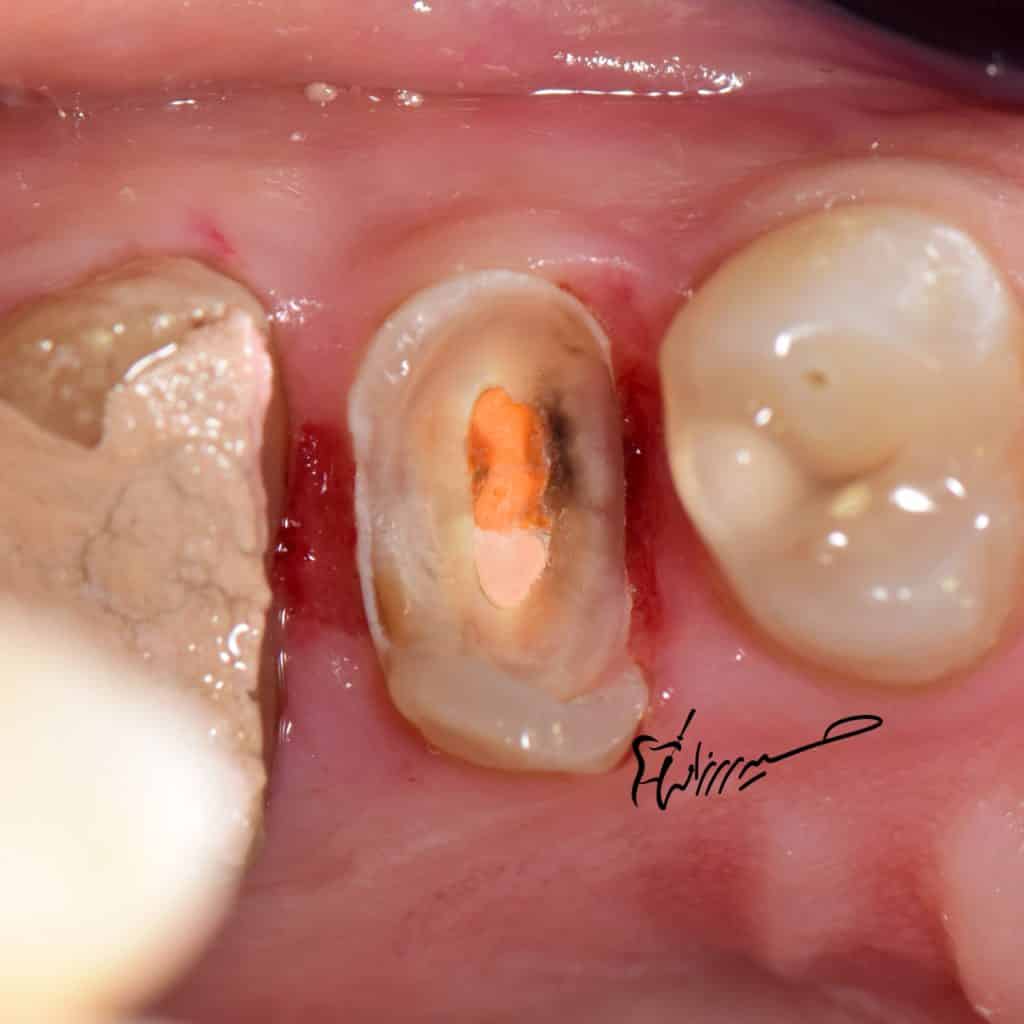

Bad RCT need re treatment

deep margin must elevate

destructive structures and there is no feruule

so adhesive options are the best